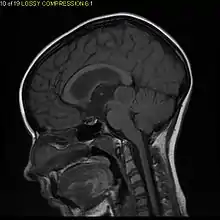

| Diagnostic method | MRI, CT scan |

Usually – depending on the interview of the patient and after a clinical exam which includes a neurological exam and an ophthalmological exam – a CT scan and/or an MRI scan will be performed to confirm the presence of a tumor. They are usually easily distinguishable from normal brain structures using these imaging techniques. A special dye may be injected into a vein before these scans to provide contrast and make tumors easier to identify. Pilocytic astrocytomas are typically clearly visible on such scans, but it is often difficult to say based on imaging alone what type of tumor is present.

Pilocytic astrocytomas are often cystic tumors, and, if solid, tend to be well-circumscribed.